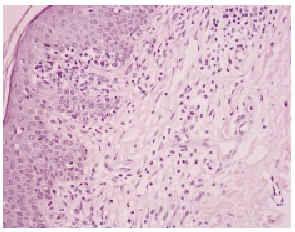

Una biopsia de la piel eritrodérmica mostraba un intenso infiltrado linfocitario pleomórfico, en banda subepidérmica, con epidermotropismo, así como fenómenos dispersos de exocitosis linfocitaria y microabscesos de Pautrier (figs. 2 y 3): el infiltrado linfocitario era positivo para CD4 y CD3, y negativo para CD22 y CD8 (fig. 4). El estudio histológico de una adenopatía mostró una infiltración específica por linfoma.

Fig. 3.--Detalle de un microabsceso de Pautrier.